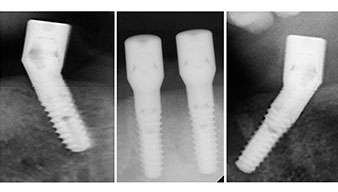

El protocolo quirúrgico de los implantes utilizados (SKY, bredent medical) prescribe una velocidad de 1 200/rpm para las perforaciones piloto (figs. 7-9).

Fig. 7

velocidad de 1 200/rpm

Fig. 8

Fig. 9

Este valor se corresponde con la posición siguiente del ajuste predefinido en Implantmed. Aquí se aprecia la inclinación de aproximadamente 45 grados del contra-ángulo de W&H hacia medio caudal en la región de la pieza 45 para preservar el nervus mentalis. El foramen mentale sirve como orientación anatómica para todas las perforaciones en esta zona. Las perforaciones siguientes se realizaron con una velocidad reducida de 300/rpm (figs. 10 y 11).